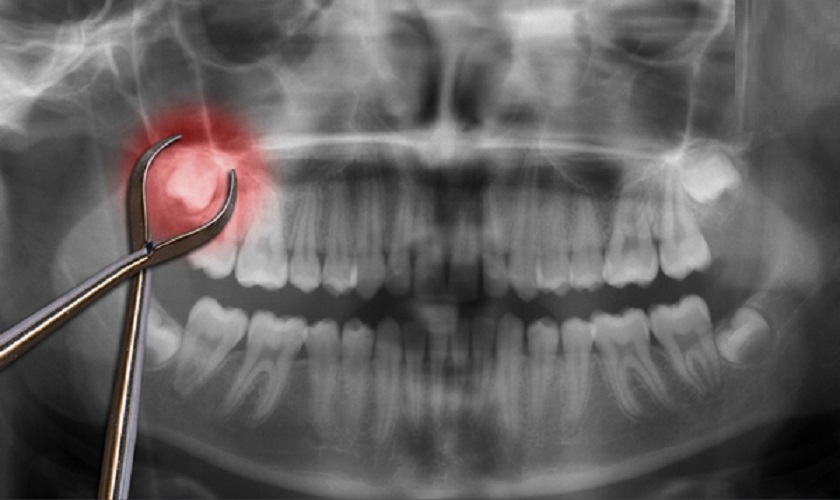

- Trường hợp không mọc răng khôn nhưng vùng nướu ở vị trí trong cùng lại bị đau nhức thì có thể chiếc răng này đã mọc ngầm bên dưới nướu. Lúc này, các bác sĩ khuyên bạn nên tới phòng khám nha khoa có chất lượng, uy tín để khám và tiến hành nhổ răng khôn mọc ngầm sớm nhất có thể.

Nên nhổ răng khôn sớm nếu chúng mọc ngầm